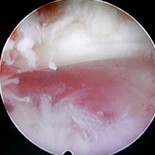

A total of 69 obese patients with LDH (35 males and 34 females; age range, 24 to 43 years; median age, 34 years) were included in this study. These patients had undergone TED from March 2011 to December 2015 in the Third Hospital of Hebei Medical University. Their clinical and follow-up data were prospectively analyzed. The degree of pain and disability were measured on the basis of the Visual Analog Scale (VAS) at 1 day before surgery, immediately after surgery, and 3 months after surgery. Neurologic functions were measured on the basis of the Japanese Orthopaedic Association (JOA) system 1 day before surgery and 3 months after surgery. The MacNab score at last follow-up was recorded to evaluate the early clinical efficacy. Complications during and after the operation were recorded to evaluate the safety of surgery.

Two patients experienced abnormal sensations in the export nerve root zone postoperatively, which disappeared after 3 days of treatment with dehydration and administration of hormone (dexamethasone). Three cases of recurrence were observed at 6 months, 7 months, and 9 months postoperatively; they were scheduled to receive total laminectomy combined with bone grafting internal fixation. A total of 67 patients were followed up for 3–23 months and mean follow-up was 11.8 months. The VAS scores at postoperative 3 months and 1 year were significantly reduced compared to that before the operation, with significant differences between them (t=43.072, P<0.05; t=43.139, P<0.05). The JOA scores at last follow-up postoperatively was significantly higher than that before surgery (t=–60.312, P<0.05). At the last follow-up, 17 cases (25.3%) had excellent outcomes, 39 (58.2%) good, 7 (10.4%) fair, and 4 (5.9%) poor. Overall, 83.5% of patients had excellent or good rates.